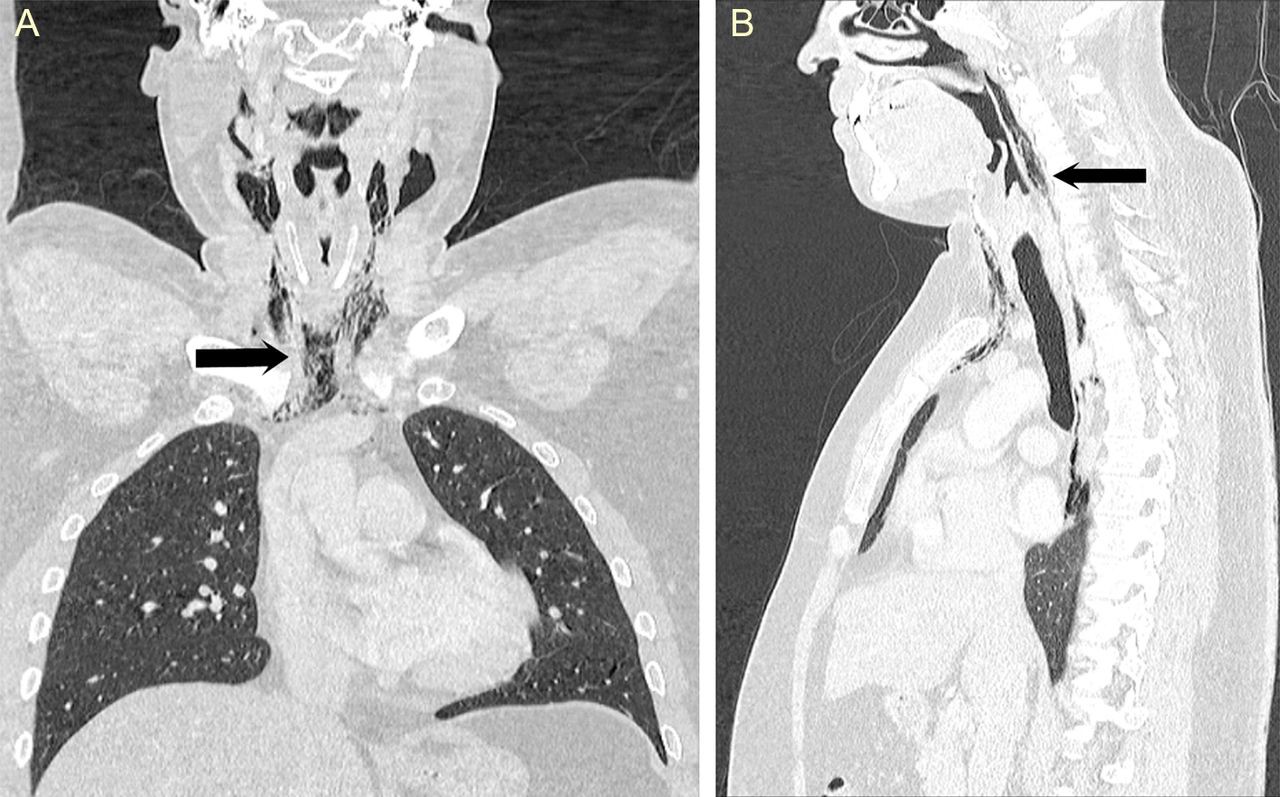

Các bác sĩ đến từ Leicester (Anh) đã đề cập đến ca cấp cứu của người đàn ông 34 tuổi bước vào phòng cấp cứu với những triệu chứng như đau nhức, khó khăn khi nuốt, nói chuyện và một cảm giác "lộm cộm" trong cổ họng bị sưng. Bệnh nhân này cho biết, những vấn đề này bắt đầu khi anh kìm nén cơn hắt hơi mạnh bằng cách bịt mũi và ngậm chặt miệng. Sau khi chụp X quang, nhận thấy có các vệt không khí ở phần ngực và cổ, các bác sĩ tiếp tục chụp CT và phát hiện ra áp lực của cơn hắt hơi bị nén kia đã xé rách mô mềm cổ họng.

Ảnh chụp X quang của bệnh nhân.